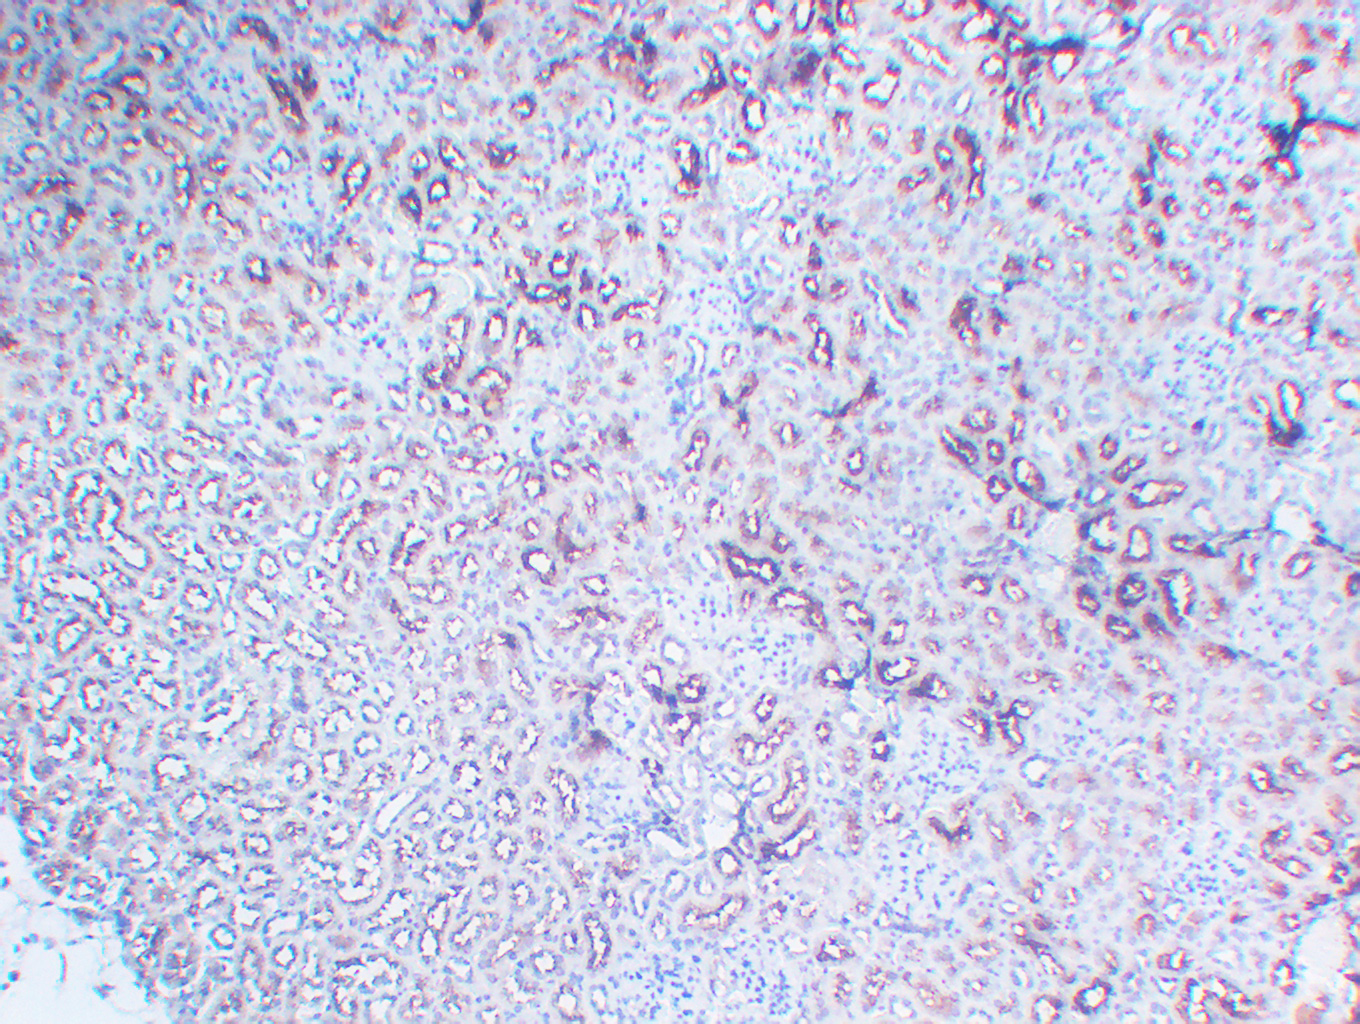

WB, IHC, IF, IP

Optimal working dilutions should be determined experimentally by the investigator; Suggested starting dilutions are as follows:IHC 1:50-300; IF 1:200.

α-tubulin Monoclonal Antibody(8F11) AbFluor™ 680 Conjugated specially designed for your Immunofluorescence analysis.

α-tubulin Monoclonal Antibody(8F11) AbFluor™ 680 Conjugated specially designed for your Immunofluorescence analysis.